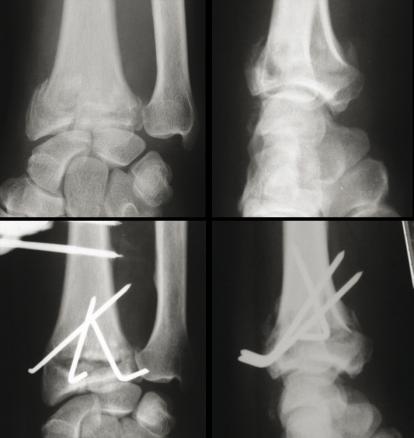

Fracture extra-intra-articulaire à déplacement postérieur : (Haut, gauche) Radio de face. (Haut, droite) Radio de profil. Traitement : on retiendra que la plaque antérieure corrige bien les déplacements antérieurs les broches corrigent bien les déplacements postérieurs, et le fixateur externe corrige bien le raccourcissement. Il faut souvent associer plusieurs méthodes. (Bas, gauche) Radio de face. (Bas, droite) Radio de profil.